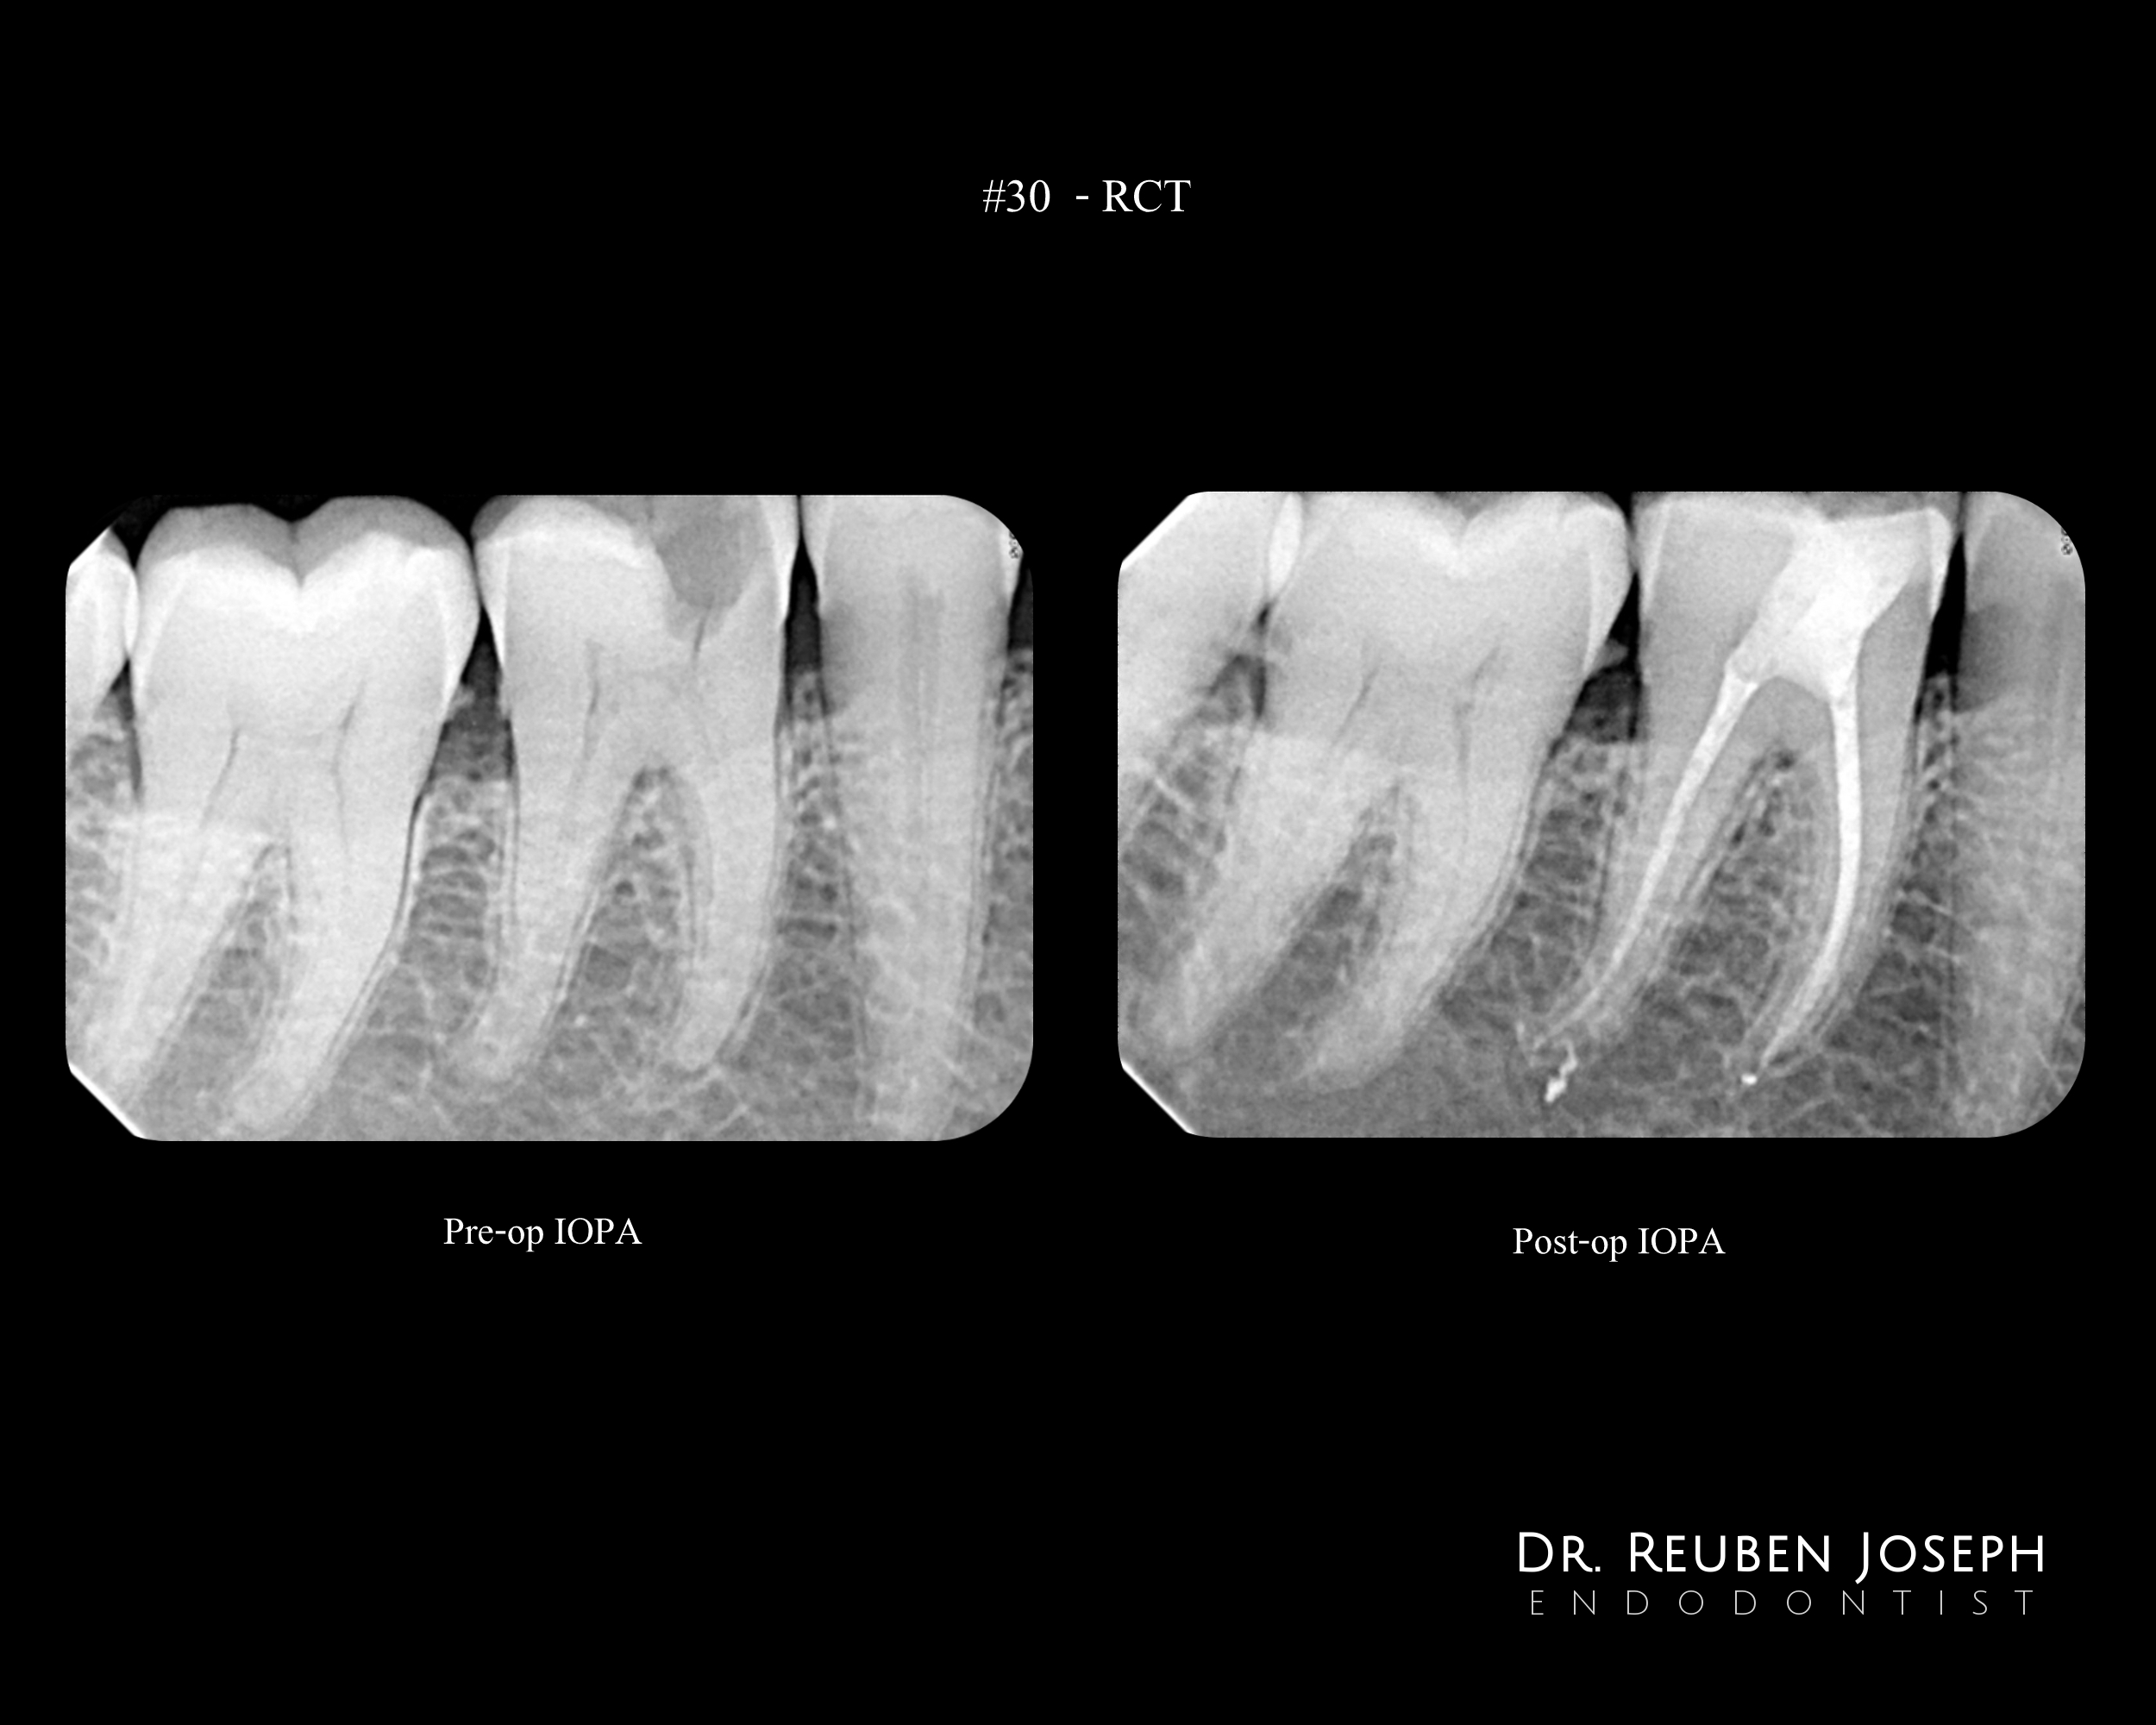

#30 Pulpitis. Caries involving the ML cusp. Caries driven access planned

Mb located in the middle of the floor and the dentinal map suggested a ML orifice present almost on the lingual wall of the tooth unlike the usual. I had to stick to what I could see rather than go to the usual co-ordinates to locate the ML canal.

ML troughed out and canals shaped and obturated using WVC